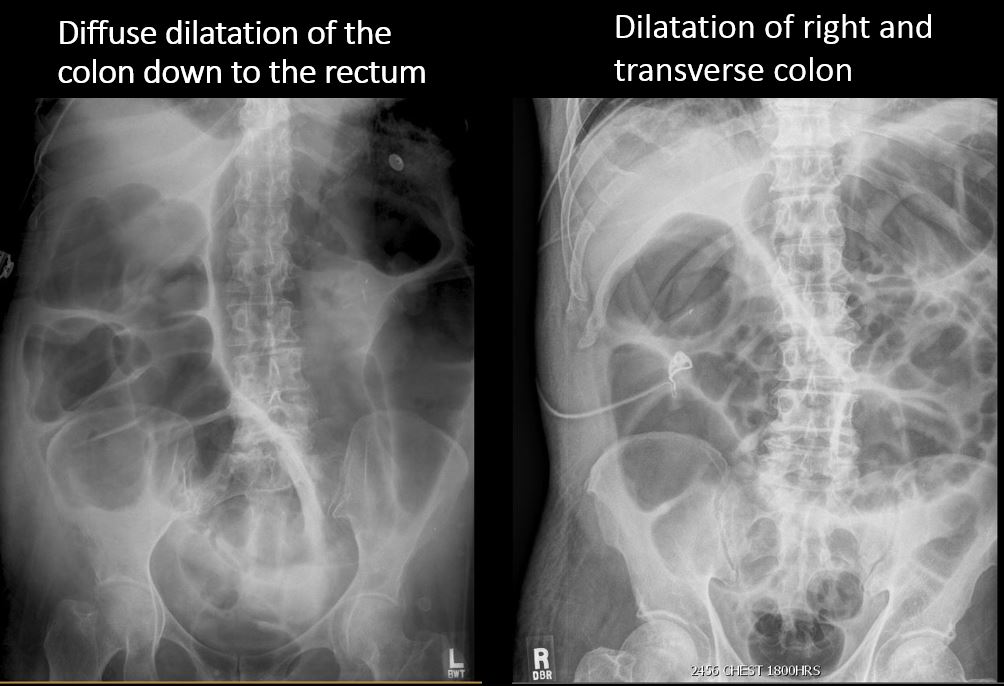

There is retroperitoneal air outlining the right psoas muscle likely from duodenal perforation, from recent endoscopy. There are a few distended loops of small bowel in the mid and lower abdomen.

Notify the clinical team verbally and immediately about retroperitoneal air likely indicating duodenal perforation from recent endoscopy.